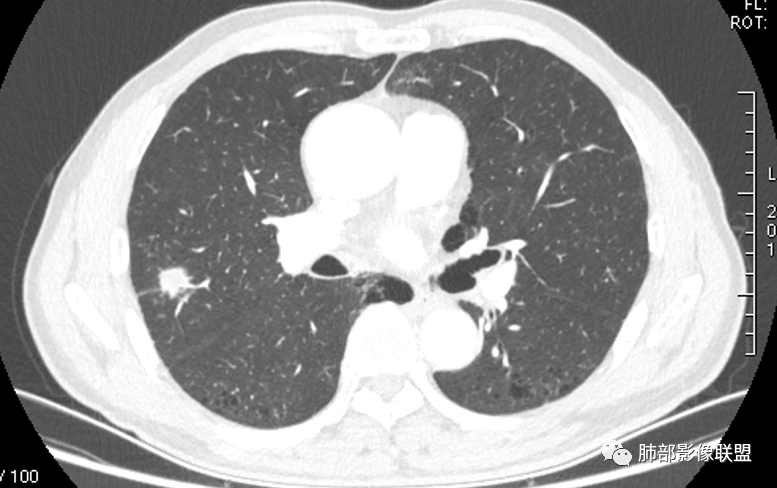

晨读:双肺胸膜下多发小气囊,大小不一,右肺结节,内部可见小空洞,洞壁光滑,厚薄不一,偏心性生长,近段血管束增粗,有分叶,毛刺(软),有晕征,平扫密度尚可,增强后不均匀强化,可见低密度坏死,及部分血管穿行,体检发现,考虑恶性:腺癌,鉴别炎性结节

右上叶结节,轻分叶,结节有长短不一毛刺,结节周围GGO边界清,有血管集束征,肺窗结节周围似可见卫星灶,可见鬼脸征,良恶性征象都有,但GGO边界清,浸润性腺癌耍考虑,临床症状轻微,体捡发现,似可见卫星灶和鬼脸征,炎性肉芽肿TB或隐球菌要鉴别。

影像学改变:

1.右肺上叶后段类圆形结节影,密度不均,有坏死空洞,坏死比较彻底,内外壁都较清楚。

2.病灶有浅切迹,没有深分叶,毛刺大多细长且柔软。

3.可见棘状突起及胸膜牵拉,但未见胸膜凹陷。

什么意思?结节影有牵拉的动作,但似乎“出工不出力”,收缩力羸弱!

4.病灶轻到中度强化。病灶内血管走行较完好,病灶旁血管局部显示粗大。

5.支气管关系不确定。

6.灶周见小结节影(卫星灶),边界不甚清晰。